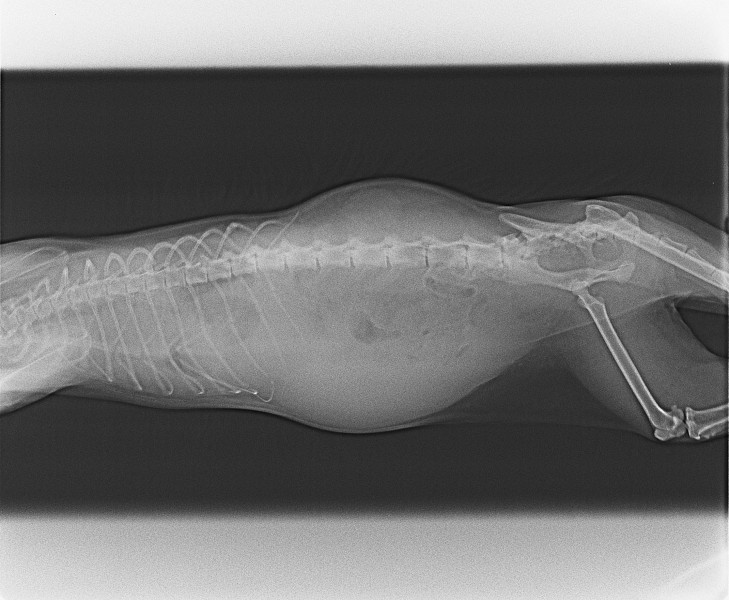

Добрый день. Пишу по просьбе хозяйки кошки. Около месяца назад 6-летняя кошка стала мало двигаться. Дышит с трудом животом. Практически ничего не ест, но пьет воду. Видимо, есть небольшое кровотечение в районе живота или груди, потому что на коврике остаются следы крови. Не идет на руки с детства, поэтому нет возможности взять в руки и проверить. С трудом отвезли к врачу и сделали снимки. Подозрение на травму внутренних органов. Прикладываю снимки. Можно ли что-то определить по ним? Можно ли спасти кошку и какой может быть диагноз? Спасибо.

предварительно по снимку в грудной полости есть свободная жидкость, также возможно и в брюшной полости. Тут нужны не только снимки, но и полноценный очный осмотр. Нужно понять, что кровит. Это может быть новообразование молочных желез, например. Также нужно сдать анализы крови на общий клинический и биохимию. Диагнозы в такой ситуации могут быть разные, метастазы в грудной клетке и выпотной плеврит, вирусный перитонит кошек, хроническая сердечная недостаточность и другие. Лечение и прогноз зависят от причины. Ситуация тяжелая и однозначно требует точного понимания и очного приема.